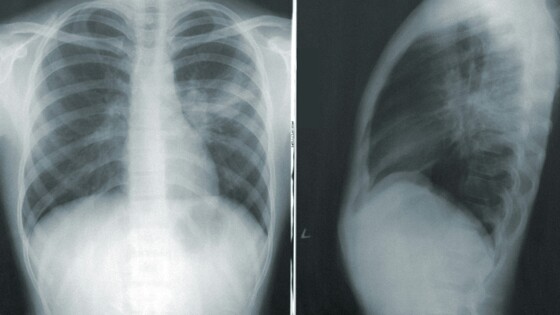

Терапевт назвал отдышку первым симптомом «серьёзного» поражения лёгких

О развитии пневмонии также свидетельствуют высокая температура и сильная слабость.

«Люди должны знать, что если у них развиваются симптомы ОРВИ, нужно хотя бы сделать экспресс-тест. Если это COVID-19, обязательно связаться с врачом для того, чтобы он успел назначить как можно быстрее противовирусные средства, если есть показания. Первое, конечно, одышка. Если она развивается, это может свидетельствовать о серьёзном поражении лёгких. Очень сильная общая слабость, температура выше 38,5. Разные серьёзные болезни, которые есть у пациентов — это диабет, ожирение, сердечная недостаточность, ишемическая болезнь сердца, поражение почек, то здесь общий профиль риска очень важный. Есть специальные шкалы, по которым можно посчитать это всё, уровень сатурации ещё учесть. Его падение ниже 95 и тем более ниже 93 — это важно».